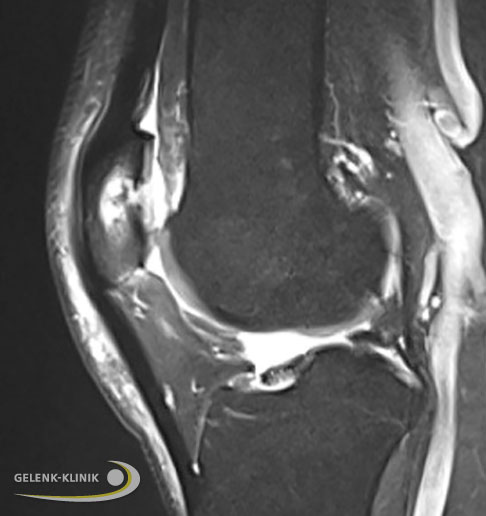

Nachuntersuchungen durch MRT bestätigen eine gute Regeneration des Knorpeltransplantats

Nachuntersuchungen durch Magnetresonanztomographie (MRT) zeigen im Verlauf nach einer Minced Cartilage-Operation eine sehr gute Qualität des Knorpelersatzgewebes und die Wiederherstellung des subchondralen Knochens. Das Minced Cartilage-Verfahren kann sicher angewendet werden und die Komplikationsraten sind nicht höher als bei anderen Knorpelersatztherapien.

Nach 9 Monaten, seitlich MRT-Aufnahmen des gleichen Knorpelschadens 9 Monate nach operativer Knorpelchips-Transplantation (links seitlich, rechts Querschnitt). © Gelenk-Klinik Nach 9 Monaten, quer Der Gelenkknorpel ist sehr gut wiederhergestellt und das Transplantat hat sich in die Umgebung integriert. Während des Regenerationsprozesses hat sich auch das Knochenmarködem der Kniescheibe zurückgebildet. © Gelenk-Klinik